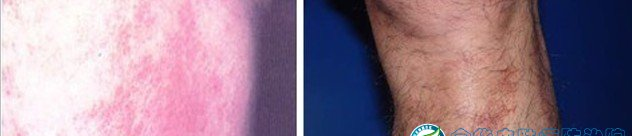

皮炎是一种常见皮肤病,表现为红斑,表面有针尖至米粒大小的丘疹、水疱、渗透液、结痂及脱屑,也可呈现苔藓样变,自觉瘙痒,日晒和遇热后会使症状加重等现象。医生建议,对于已经出现皮炎或者过敏症的人,应到正规医院诊治。下面是皮炎的图谱,如果你怀疑自己得了皮炎,可以对照下面谱图;

三、接触性皮炎